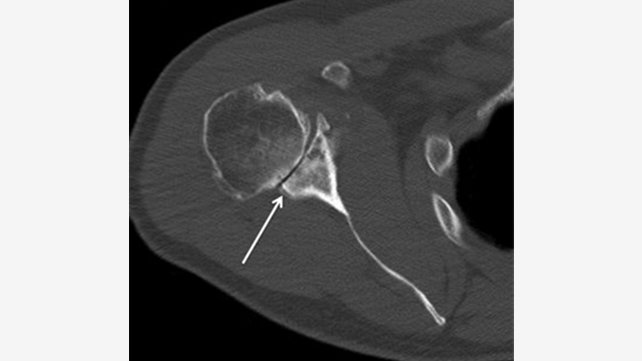

Humeral head replacement with glenoid reaming arthroplasty (ream and run) was developed as an alternative glenoid treatment that eliminates the risk of implant loosening. In this procedure, the glenoid bone is reamed in order to restore a smooth surface, allowing for more motion and less pain. (See figure 6.) Excellent results have been reported that show significant improvement in function and pain in patients younger than age 55.

(Fig. 6) X-rays of a 52-year-old, active male after humeral head replacement and glenoid reaming arthroplasty.